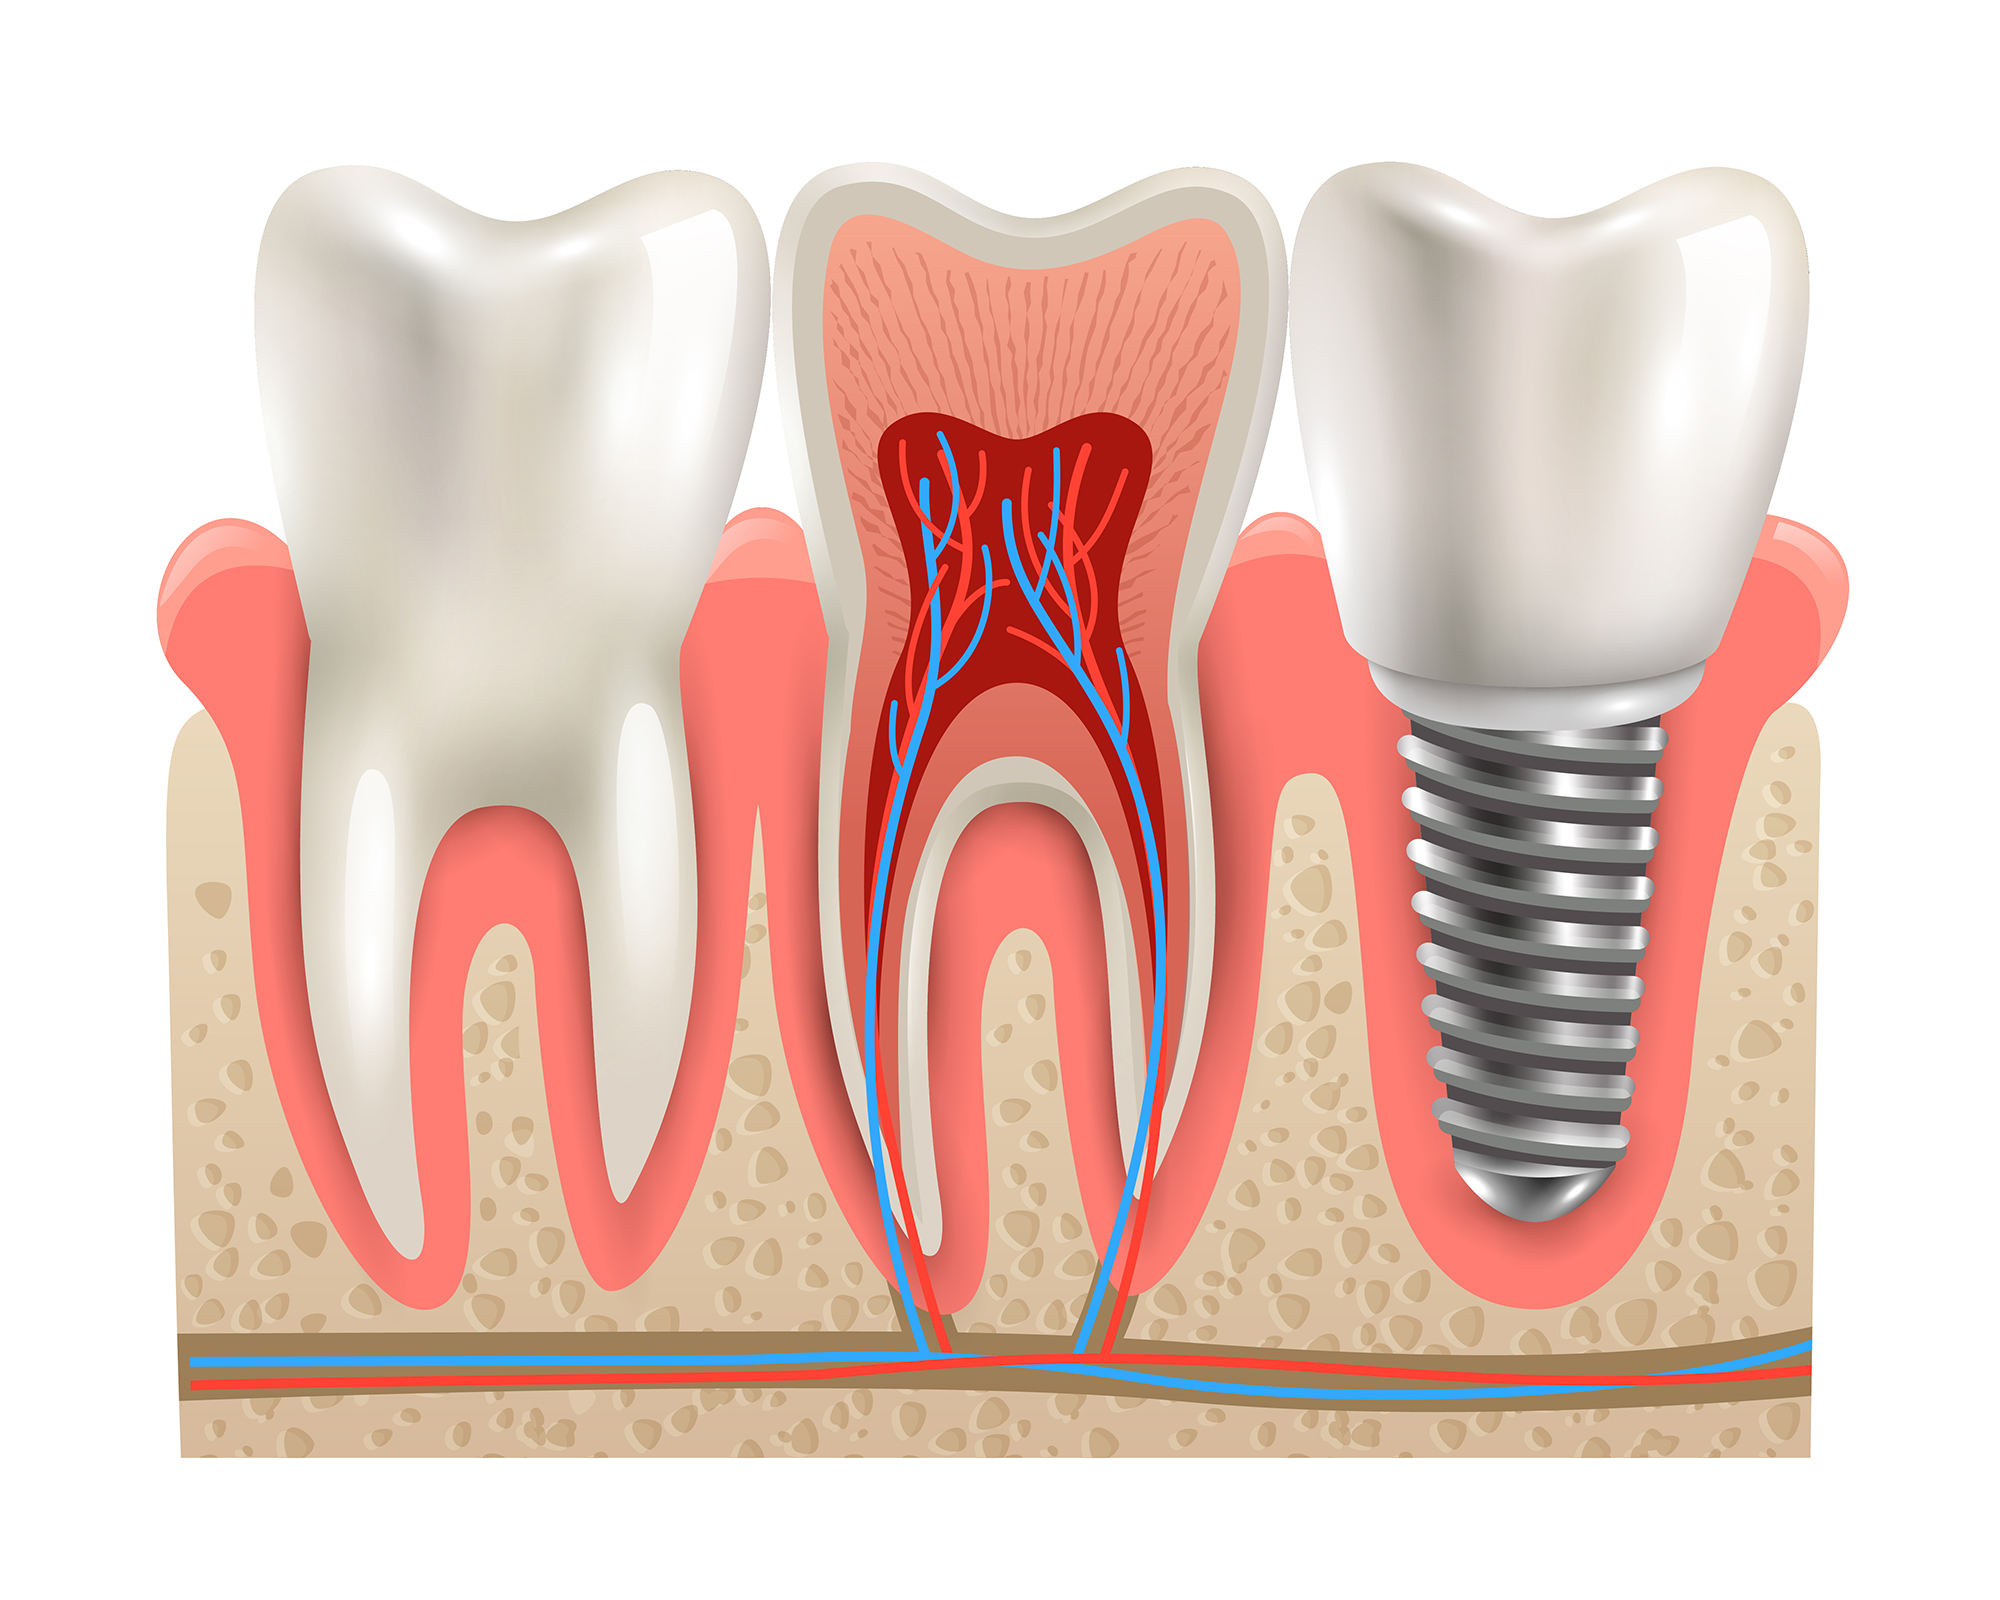

İmplant, vücut içerisine ve canlı dokulara yerleştirilen cansız maddeleri ifade eder. İmplantlar, eksik olan bir veya birkaç dişin işlev ve estetiğini iade etmek için çene kemikleri içinde açılan yuvaya yerleştirilen genellikle titanyum esaslı vida veya kök şeklindeki yapılardır. Dental implantlar, biyolojik uyumlu materyallerden yapılmış suni köklerdir.

İmplantlar doğal dişlerden farklı olarak, çene kemiği ile direkt olarak birleşirler. Çene kemiğinin implantı kabul edip sarması gerekir. Bu süreci olumsuz etkilememek için implantlar üzerine protezler, uygulanan implant çeşidine göre değişmekle beraber 4-6 hafta sonra takılır.Bu geçiş döneminde estetik amaçlı çiğneme fonksiyonunda geri planda kalan geçici protezler takılabilir.

İmplantlar çekim sonrasında yapılabildiği gibi, önceden çekilmiş diş boşluklarına da yapılabilir. İmplantın yerleştirileceği bölgede yeterli kemik miktarı olmasa bile çeşitli yöntemlerle uygun zemin oluşturulabilir. İmplant tedavisi 18 yaşının üzerinde, ağız hijyenine dikkat eden, aşırı sigara kullanmayan, kemik hastalığı olmayan, kontrolsüz sistemik bir hastalığı olmayan tüm bireylerde uygulanabilir.

Çocuklarda ve kemik gelişimini tamamlamamış bireylerde implant ekimi yapılmamaktadır. Ayrıca hamileler, yüksek tansiyon, diyabet, hemofili hastalıklarda ve radyoterapi, kemoterapi, uzun süreli kortizon tedavisi gibi tedaviler gören hastalarda yapılamaz. Bugüne kadar yapılan, literatüre giren klinik çalışmalarda başarı oranı % 95-100 dür. İmplant, ağız hijyenine dikkat edilirse ömür boyu kullanılabilir.